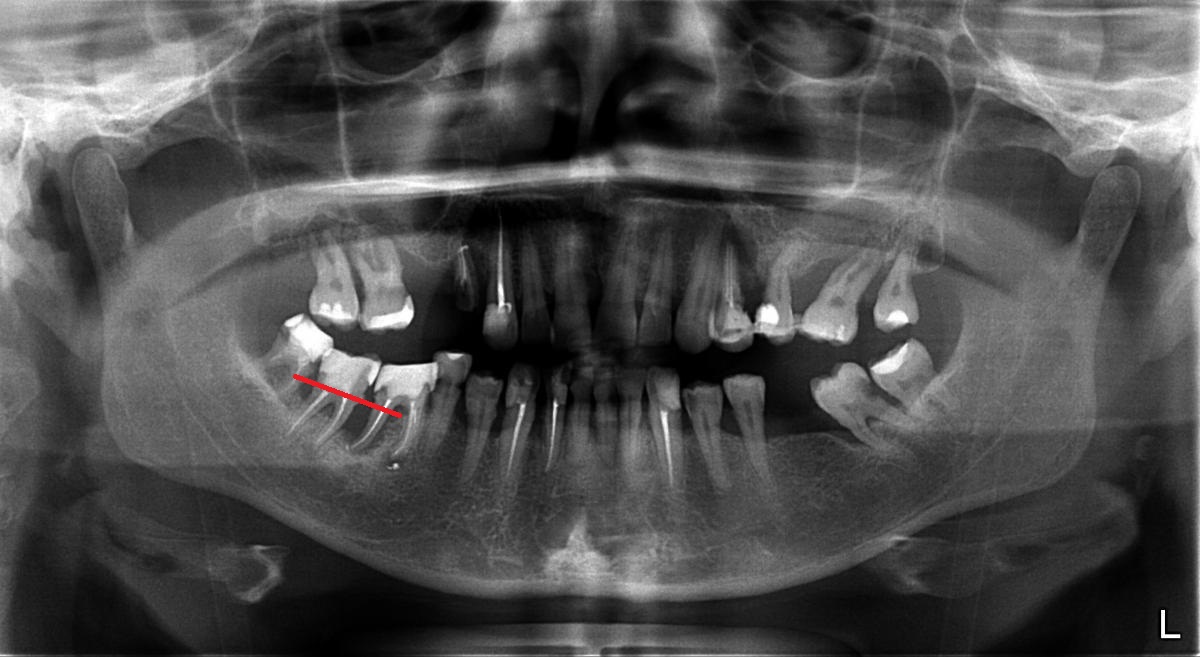

Примеры ортопантомограмм и их анатомия

Раздел: Фотоэссе